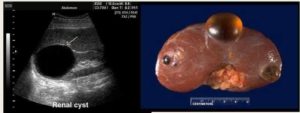

Если вам поставили диагноз киста на левой или правой почке, мы поясним, что это такое. Урология дает портрет и характеризует ее так — структурное доброкачественное новообразование, полое внутри и заполненное желтоватого цвета жидким экссудатом.

Это так если по заумному и научному, для более доступного понимания — представьте себе небольшой шарик или капсулу, в которые налили воду.

Обязательно потребуется детальное ультразвуковое изучение в результате, которого будет максимально уточнены параметры локализации, количество кистозных образований, их плотность, наполненность, а также насколько они деформируют и влияют на “соседей”: печень, селезенку, легкие, диафрагму.

Киста почки (нефрона) – это урологическая патология, характеризующаяся формированием в различных ее структурах полостных доброкачественных образований, заполненных жидким субстратом.